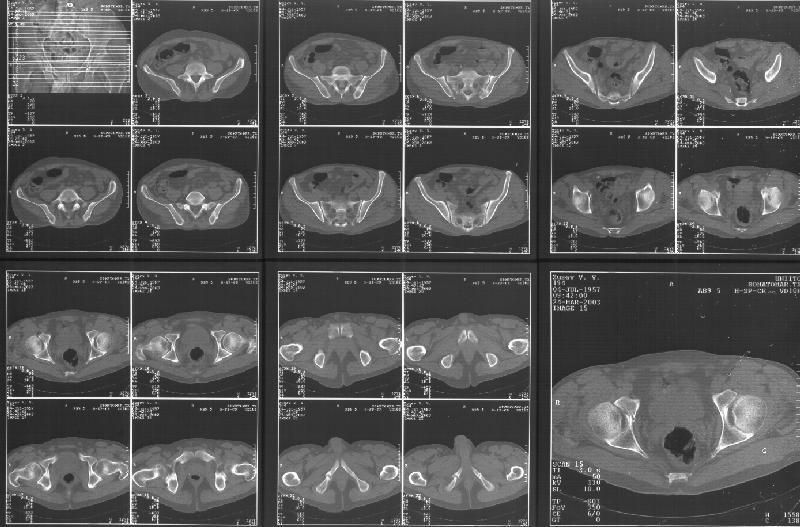

Прилагаю свежую КТ таза.

Картинки см. ниже, левая - с экранным разрешением, вторая - полноразмерная, ~900 кб.

КТ в экранном разрешении

Полноразмрная картинка, около 900 кб

Based on the CT images you provided, he appears to have a nonunion of the the right ischium, which would explain his symptoms. General principles of treatment of hypertrophic (which this appears to be) nonunions suggest rigid fixation, but I'm not sure what the best approach would be. Could get a lag screw across the fracture through a Kocher-Langenbeck approach or plate osteosynthesis through direct ischial approach, but perhaps Chip, Adam or someone with more pelvic fracture experience could enlighten us all.

I think the CT cuts in question are on the right of the bottom row i.e.

http://www.hwbf.org/hwb/conf/alex47/image3a.jpg

Thanks for the link to the plain films and CT images.

I think this is just a pelvic ring disruption that has gone on to a non-union. The arrow is pointing to the inferior ramus non-union, and

the sup ramus is a high "root" fracture, right near the pecten. The sup ramus fracture enters the tab - you could call it an acetabular

fracture - but down here in Dallas we treat these acutely as stable pelvic ring injuries. The fracture in the anterior portion of the

acetabulum is so low it doesn't seem to cause much trouble.

His R sacroiliac joint is opened anteriorly a little bit - the "unreduced posterior lesion" Alex mentioned in his first post. My earlier post about plating, bone grafting, etc., is all wrong.

What you have is a pelvic fracture that hasn't healed after 4 months or so, with a minimal deformity.

I think what I would offer the guy is a percutaneous iliosacral screw to stabilize and improve the SI joint alignment, coupled with a perc anterior column screw to stabilize the high ramus fx. These screws aren't easy to place, and have a host of potential problems and complications. But, I think they would work.

Как Вы сами видели на томограммах, грубых деструктивных явлений крестцово-подвздошного сочленения не определяется( маркировка правая -левая сторона не видна), определяется сравнительно незначительное расширение суставной щели с одной стороны и не более того.

Виноват, первый раз не обратил внимания на возможность полноформатного просмотра томограмм. В этой связи -дополнения к своему первому комментарию: сросшийся перелом вертлужной впадины справа, L5-S1 спондилоартроз, расширение суставной щели крестцово-подвдзошного сочленения справа может компрометировать его стабильность и вызывать локальные боли, но вряд ли это может давать двусторонние проявления в нижних конечностях. Все-таки миелограмма или ЯМР желательно иметь, чтобы определиться в тактике.

Я в некотором присоединяюсь к Коллеге из Далласа:

Речь идёт о коплексном двустороннем повреждении таза с нарушением тазового кольца.

А именно: разрыв илио-сакрального сочленения справа, на этой же стороне трансацетабулярный перелом с незначительным смещением, перелом подвздошной кости слева. Исходя из вышеперечисленного, меня не удивляют двусторонние жалобы пациента. Однако, учитывая представленные снимки ЯМР и времени, прошедшим с момента травмы мне представляется пока преждевременным говорить об образовании ложных суставов. Судя по развиввшейся костной мозоли в области вышеперечисленных очагов, все переломы находяться в стадии консолидации. Вполне возможно, однако, что трансацетабулярный перелом приведёт в дальнейшем к развитию посттравматического артроза ТБ- сустава.